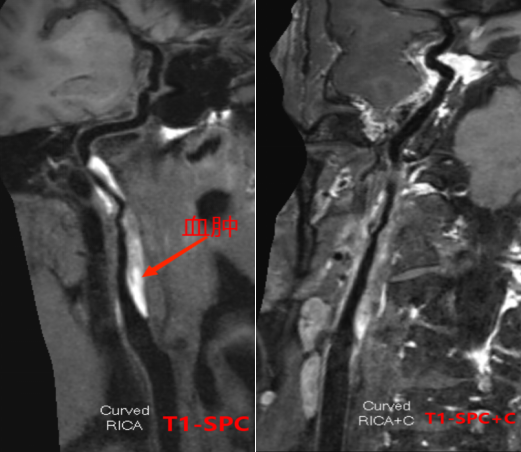

3招丨找出壁间血肿(动脉夹层)

ef67d9fa36dc94c9d4ac5fd611a15201.png

1 TOF-MRA图可见颈内动脉内膜片影

2 CE-MRA图可见颈内动脉真假腔显示

266bdc3b78e99e1e45b42d871817ee31.png

13D-T1-SPC图显示打药前颈内动脉C1C2段高亮的壁间血肿及管腔重度狭窄。

23D-T1-SPC图显示打药后血肿及相应节段血管壁都强化不明显。